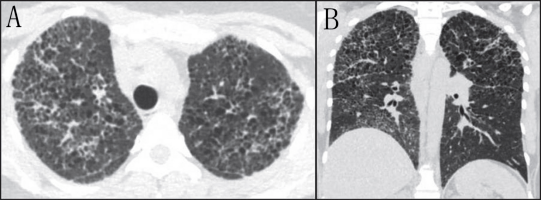

CT表现包括广泛的磨玻璃影,主要分布于中央和肺门周围区域、小叶间隔增厚、可能还有胸腔积液和淋巴结肿大。小叶内间隔增厚伴磨玻璃影可表现为“铺路石”征。囊肿较为常见,尤其在HIV感染者中,囊肿的大小、形状和壁厚各不相同,且好发于上叶(图9) (24、25)。囊肿破裂可导致气胸和纵隔气肿(24)。

9 一名33 岁男性患者的CT扫描,HIV阳性,治疗依从性差。出现呼吸困难后发现感染孢子菌病。A: 轴位示弥漫性玻璃,散在支气管壁增厚及数个大小不同的细支气管周围囊性结构。冠状面重建显示肺囊肿分布于在细支气管周围。